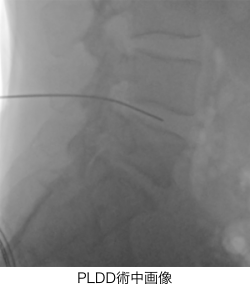

- PLDD(経皮的レーザー椎間板減圧術)

PLDDは、背中からレーザーファイバーが通った針を刺し、飛び出した髄核にレーザーを照射する治療法です。また、歯髄由来幹細胞上清液は、歯髄から幹細胞を培養した溶液の上澄みです。さまざまな成長因子が含まれているため、組織の回復を助ける作用が見込めます。

レーザーを椎間板内の髄核に照射して縮小させ、神経の圧迫を軽減する治療法です。施術に要する時間は一箇所あたり15〜30分程度と短時間なので、日帰りが可能。1mm程度の穴から治療できるため、術後の出血や痛みが抑えられることも特徴です。